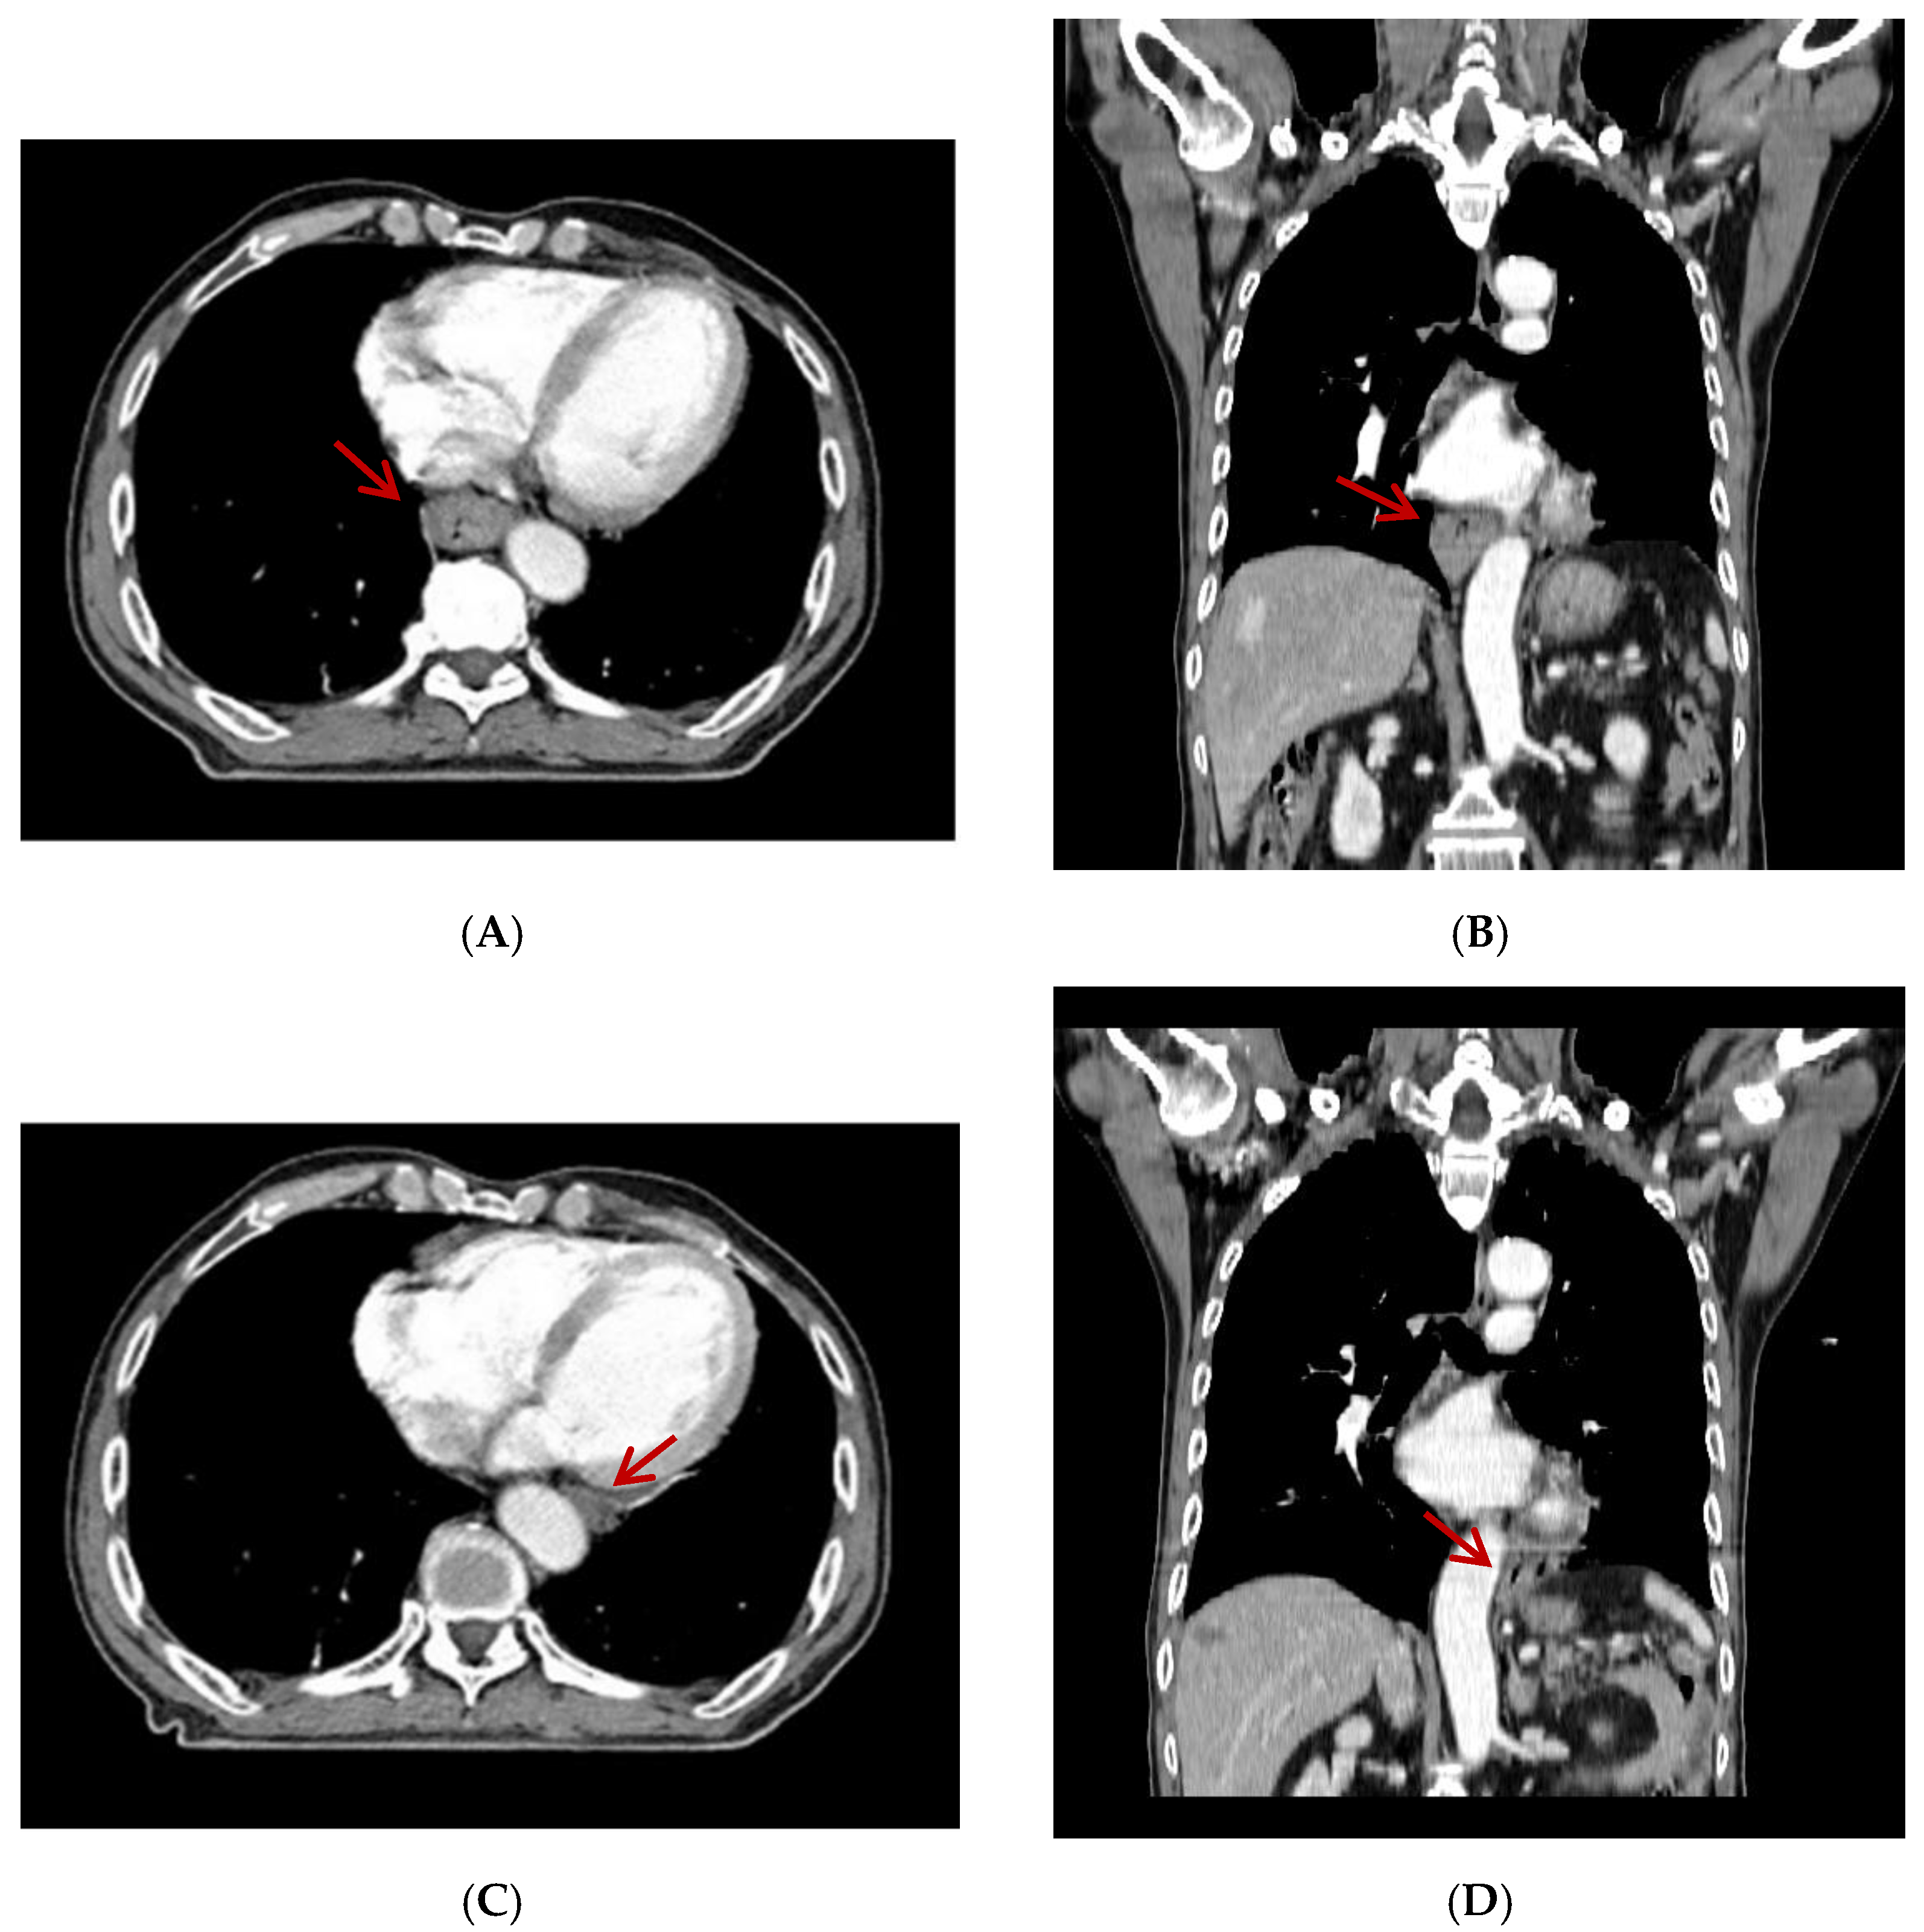

Unexpected Movement of the Esophagus across the Aorta

Choi, H.H.; Sung, S.-Y.; Ko, Y.H. Unexpected Movement of the Esophagus across the Aorta. Diagnostics 2022, 12, 1758. https://doi.org/10.3390/diagnostics12071758